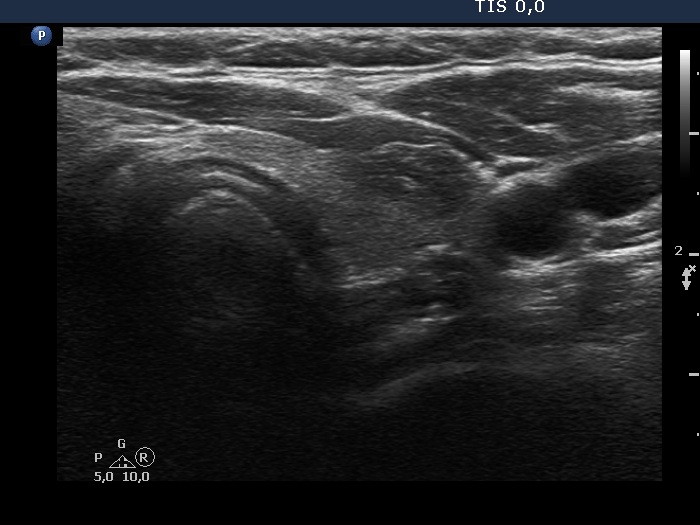

Follow-up investigation 6 years later (ultrasonographic picture 9)

Right lobe, longitudinal scan

Upper part of the left lobe, transverse scan. There is a small hypoechoic lesion.